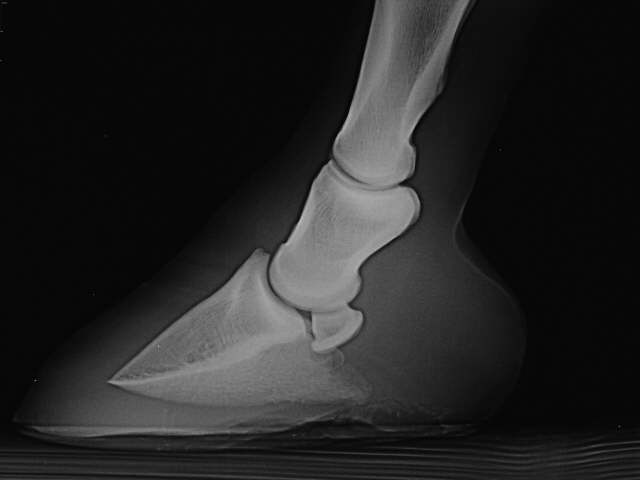

Flacher Huf

Flacher Huf mit Atrophie der Hufbeinäste und Veränderung der Kontur des Hufbeines, das Hufbein ist abgesunken.